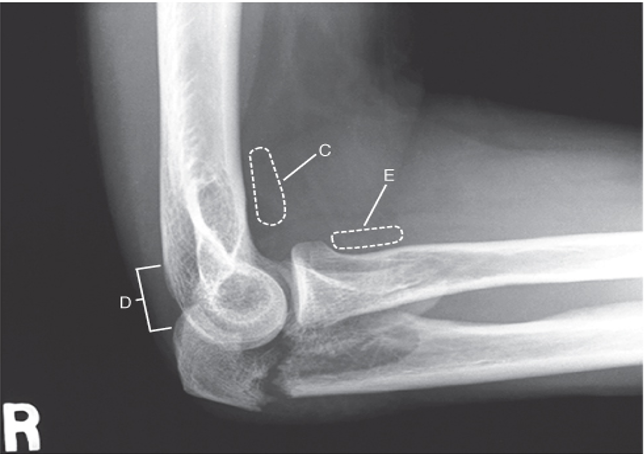

23

Q

What projection is shown here?

24

What fat pad is often seen when there is an elbow fracture?

A

Fx of olecranon process